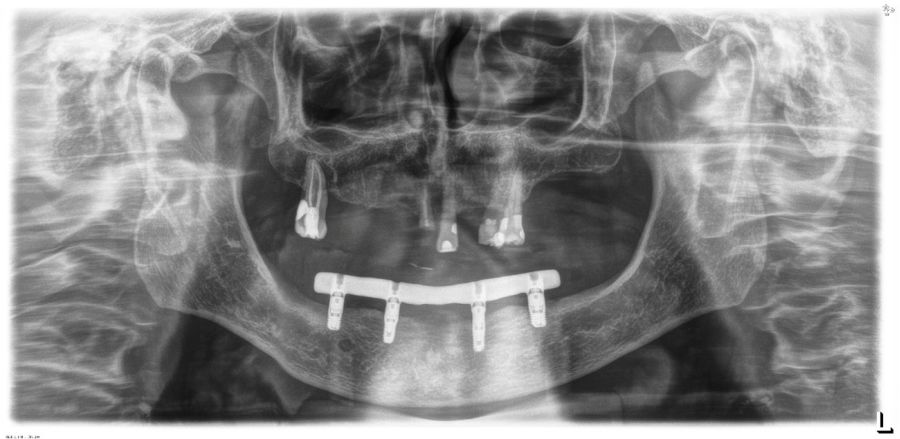

El análisis global de los 99 implantes reveló una pérdida ósea marginal media de 0,77 ± 0,26 mm en la superficie mesial y 0,79 ± 0,29 mm en la distal, valores que se mantuvieron dentro de los rangos considerados clínicamente aceptables para rehabilitaciones mandibulares. Cuando los implantes se categorizaron según su longitud, se observaron diferencias claras entre ambos grupos. Los implantes cortos (<10 mm) mostraron una pérdida ósea mesial media de 0,61 ± 0,23 mm y distal de 0,56 ± 0,22 mm, mientras que los implantes largos (≥10 mm) presentaron pérdidas significativamente mayores (mesial: 0,92 ± 0,19 mm; distal: 0,99 ± 0,17 mm). Dado que las pruebas de normalidad (Shapiro–Wilk) mostraron una distribución no normal en todos los grupos (p < 0,001), se aplicó la prueba no paramétrica de Mann–Whitney U. Los resultados confirmaron diferencias estadísticamente significativas tanto en la pérdida ósea mesial (U = 2068,5; p < 0,001) como en la distal (U = 2247,0; p < 0,005), indicando que los implantes cortos presentaron un comportamiento óseo más favorable que los implantes largos a lo largo del tiempo. Durante el tiempo de seguimiento que fue de media de 12,2 años (+/- 4,4; rango 6-23 años) no se objetivaron fracasos en ninguno de los implantes por lo que la supervivencia acumulada fue del 100%. El análisis del periodo de seguimiento mostró diferencias claras entre ambos grupos. Los implantes largos (≥10 mm) presentaron un tiempo medio de función de 14,1 ± 4,2 años (rango: 9–23 años), mientras que los implantes cortos (<10 mm) registraron un seguimiento significativamente menor, con una media de 9,8 ± 2,7 años (rango: 6–15 años). En las Figuras 3- 10 se muestran dos casos incluidos en el estudio, uno de cada situación descrita.